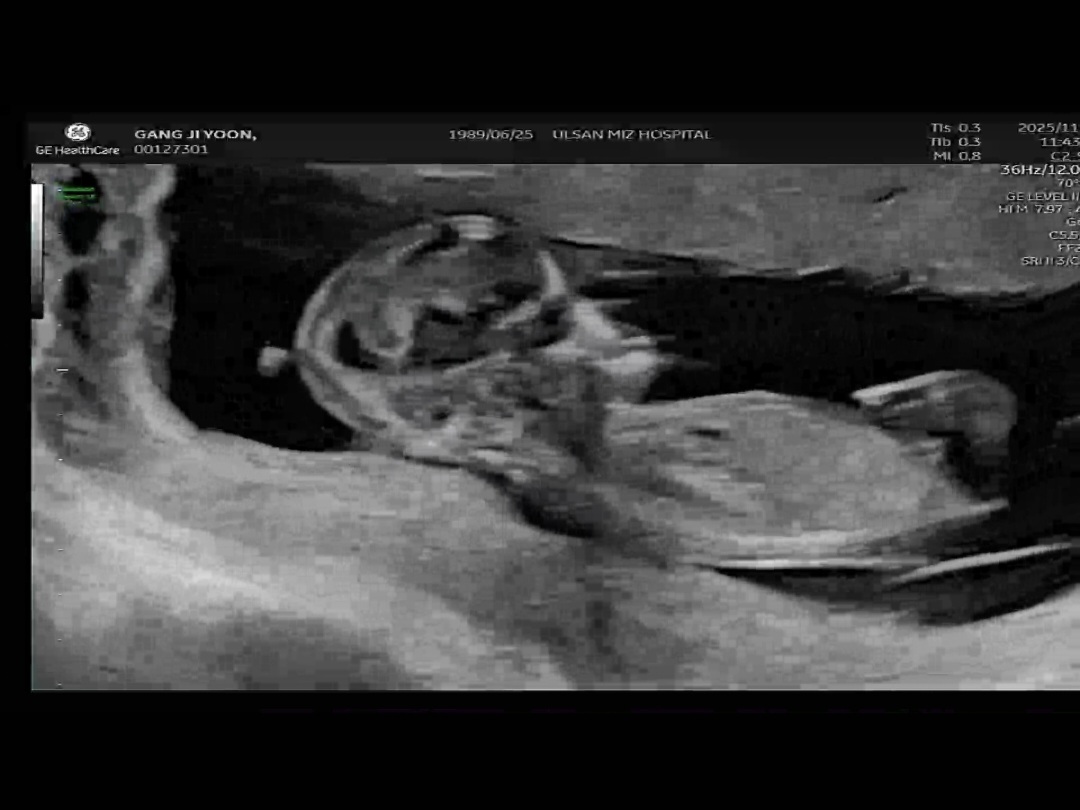

성별너무궁금해요

어떻게보이시나요?

엇 딸같은데용!

딸같아여

감사해요 제가 첫째둘째가 아들이라 정말딸이면좋겠어요 의사선생님이 한달후에봐주신다해서 한번올려봤어요 답글감사해요!!!